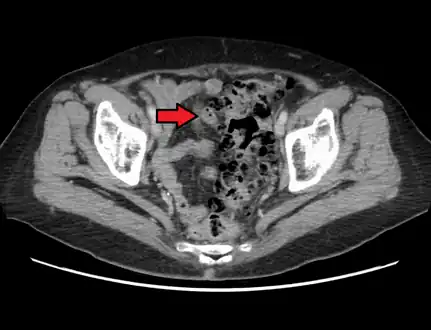

CT scan showing extensive diverticulosis of the sigmoid colon

Diverticular disease

Diverticulosis is defined by the presence of multiple pouches (diverticula) in the colon.[22] In people without symptoms, these are usually found incidentally during other investigations.

- Contrast CT is the investigation of choice in acute episodes of diverticulitis and where complications exist.